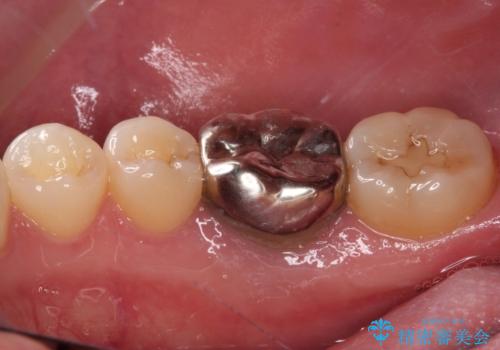

- 右下の奥歯の歯茎が腫れているとのことで来院された患者様です。

銀のクラウンが装着されていた歯は根管治療が必要であり、その奥の歯は大きな詰め物の隙間が虫歯になってしみていました。

根管治療などを行った後に、オールセラミッククラウンにて補綴することとしました。